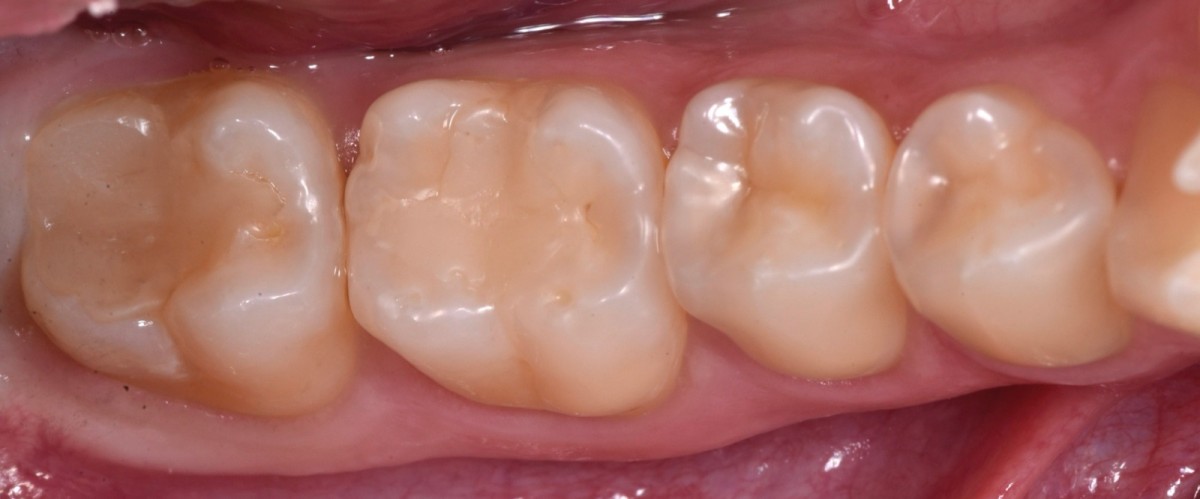

Final restorations before polishing (Fig.12).

Immediately after rubber dam removal (Fig.13).

6-months follow up (after finishing and polishing) (Fig.14).

Detail of the vestibular part, showing good health of periodontal tissues. 3.8 element will be extracted as soon as possible to avoid probing distal to 3.7 (Fig.15).

Final rx bitewings (Fig.16).